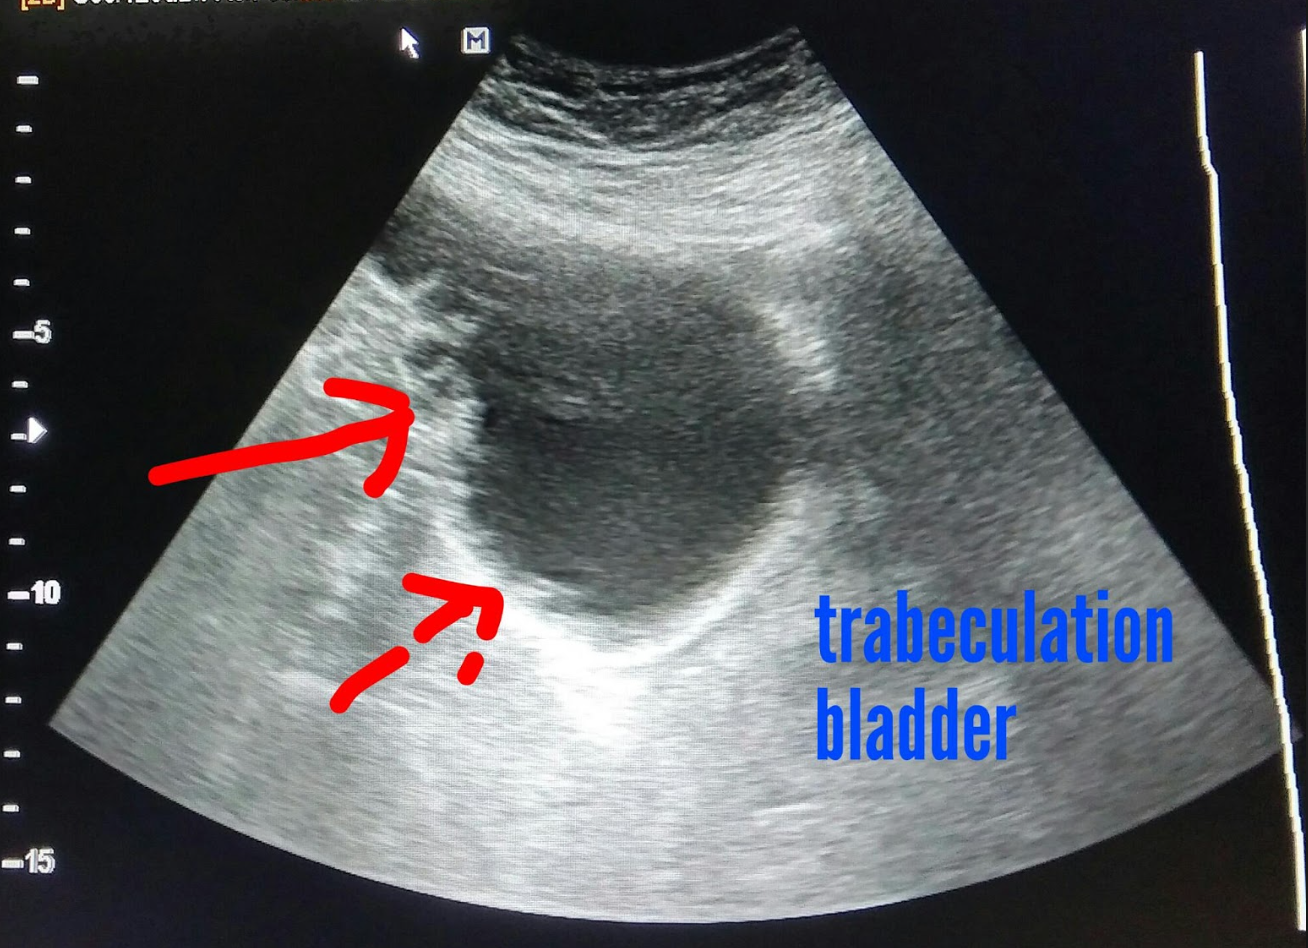

Define: poorly functioning bladder secondary to neurological disorder, detrusor muscle does not work properly

neurogenic bladder

Sono findings of neurogenic bladder (3)

- thickened bladder wall and trabeculae

- urinary retention

- distended bladder but no urgency

Chronic cystitis can lead to ___

scarring and trabeculation of bladder wall